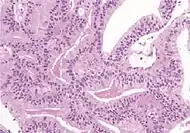

| Non acinar (or mixed acinar/ non-acinar) adenocarcinoma | Ductal adenocarcinoma | 3% to 12.7%[8][notes 1] | ![]() |

||||

Ductal adenocarcinoma may have a prominent cribriforming architecture, with glands appearing relatively round, and may thereby mimic intraductal adenocarcinoma, but can be distinguished by the following features:[10]

| Feature | Ductal adenocarcinoma | Intraductal adenocarcinoma |

|---|---|---|

| True fibrovascular cores in micropapillary architecture | Present | Usually absent |

| Cribriform lumens | Lined by pseudostratified, columnar cells | Punched out lumens lined by cuboidal cells |

| Basal cell markers | Usually negative | Usually positive |